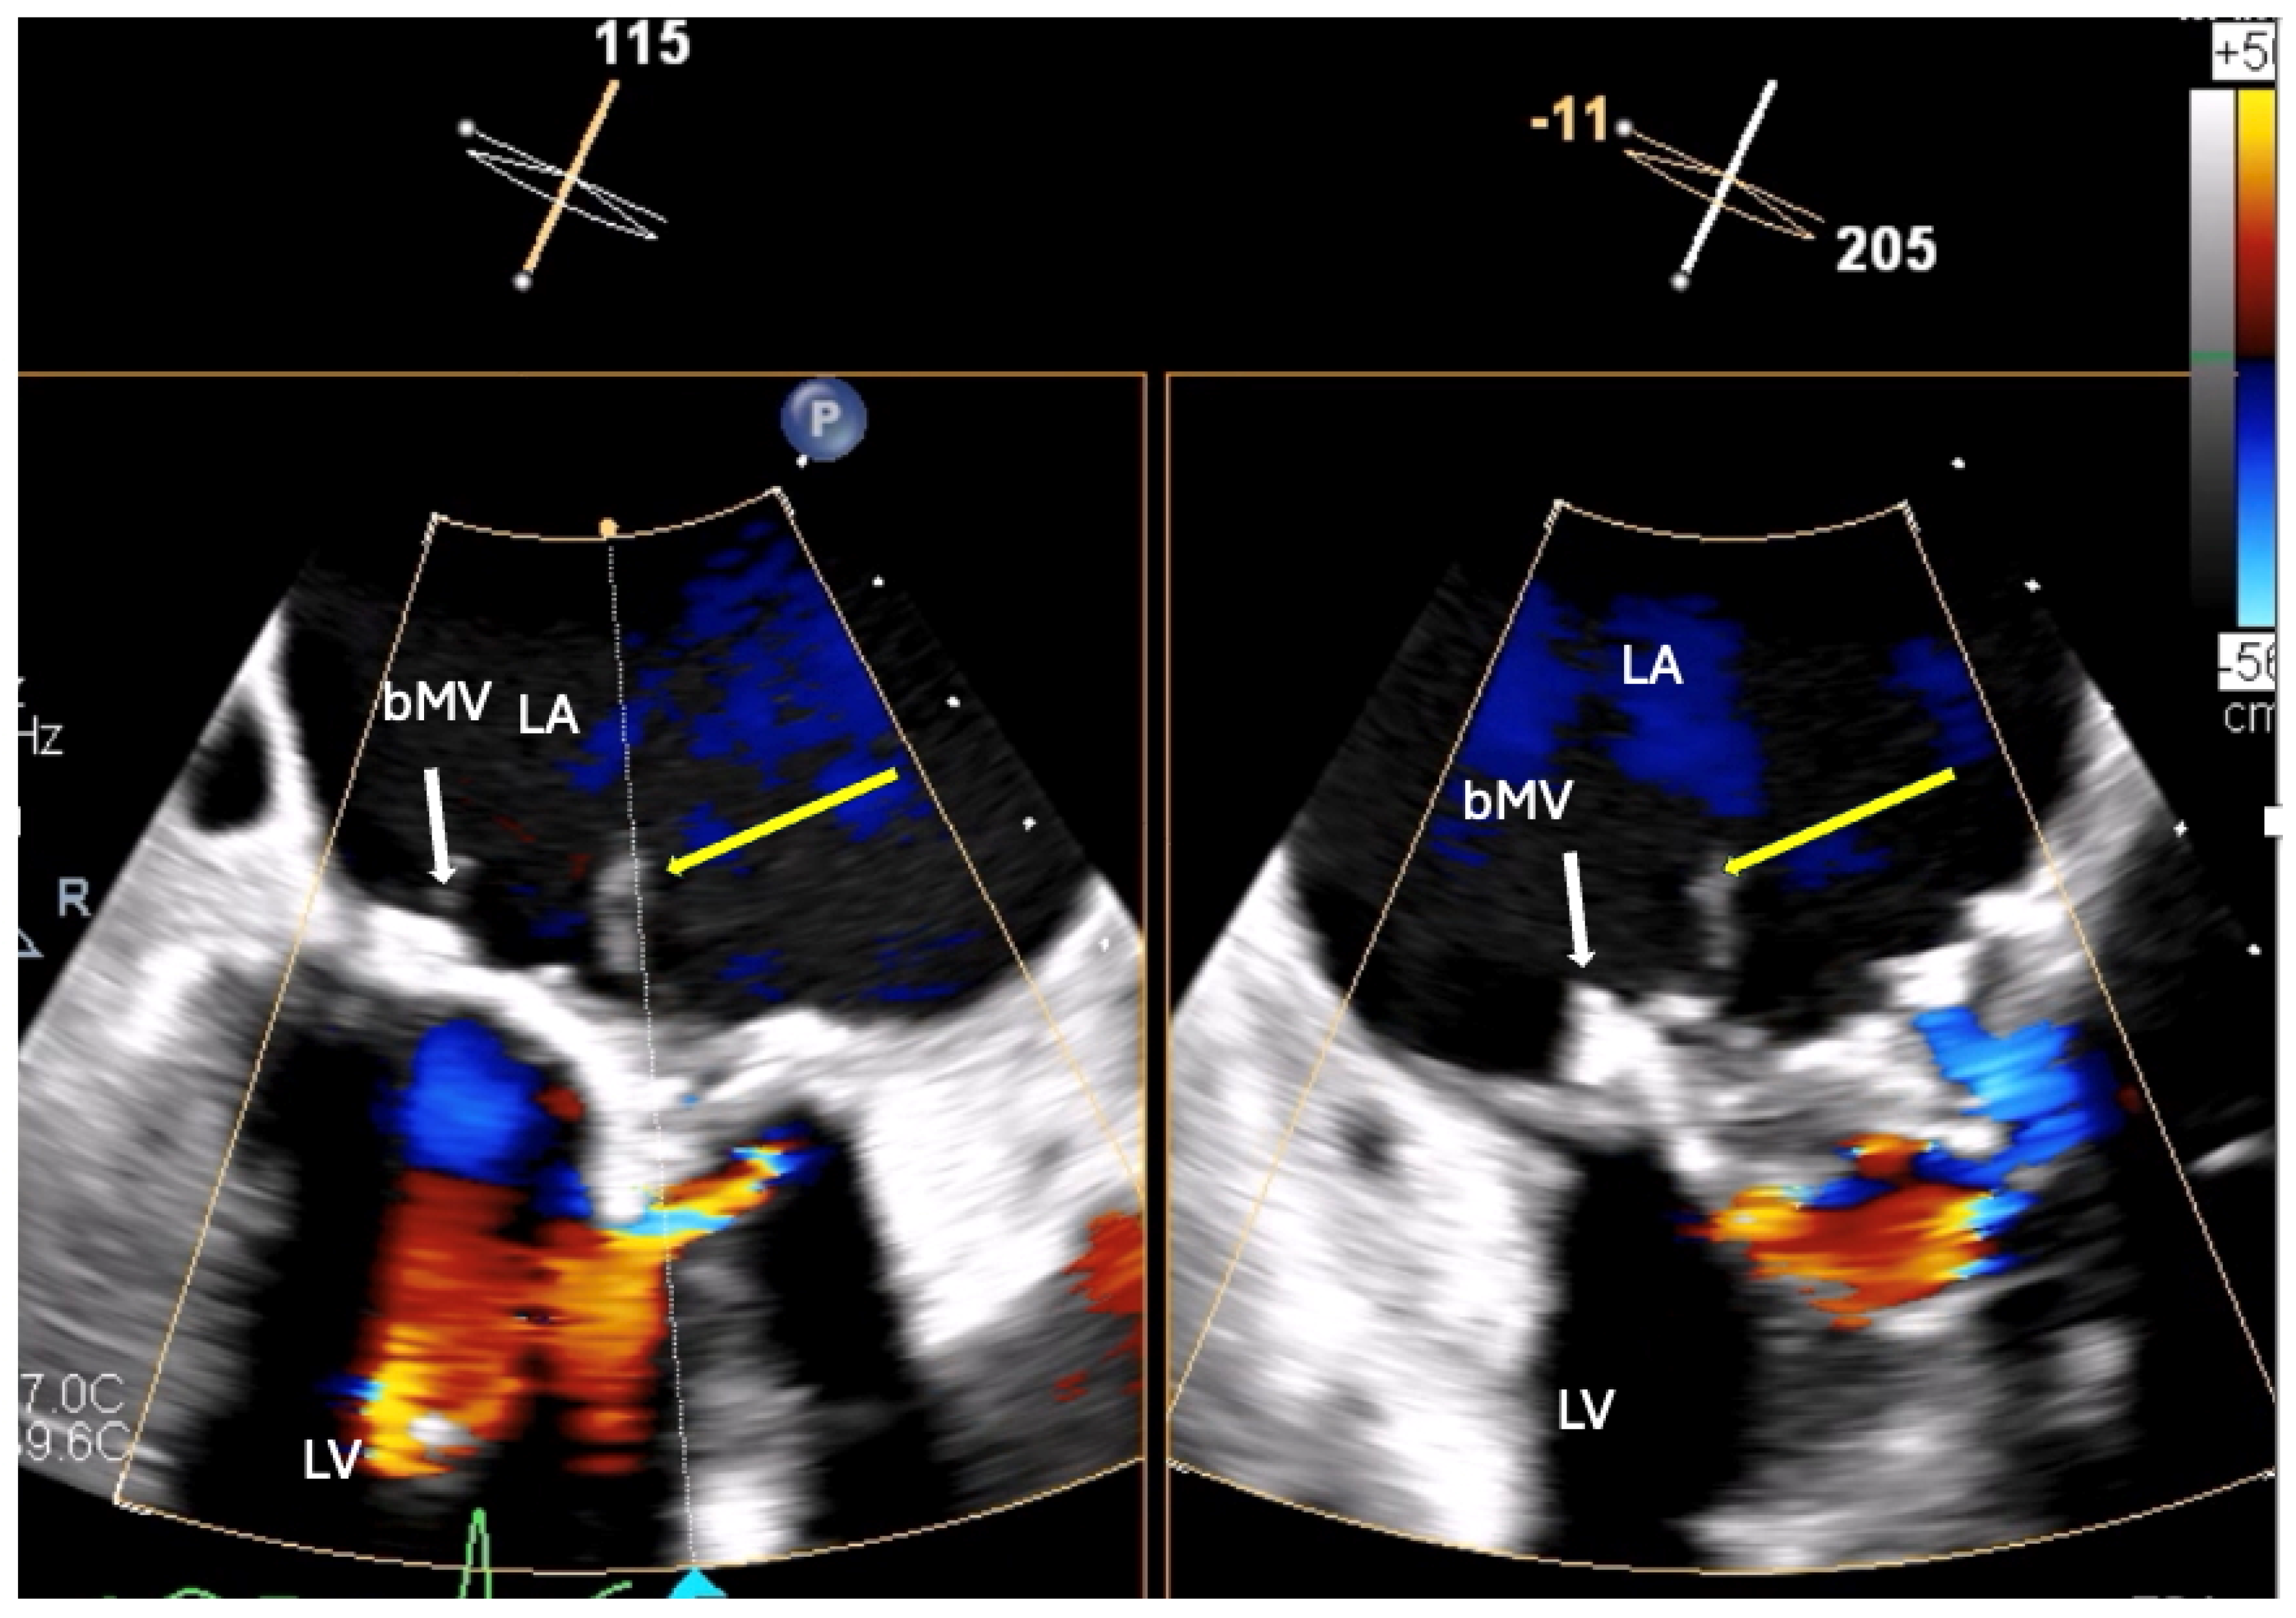

1.1.3. Case 3

2.3. The Saga of Relapsing IE of the Prosthetic Mitral Valve Causing Structural Valve Degeneration and Transcutaneous MViV Prosthesis